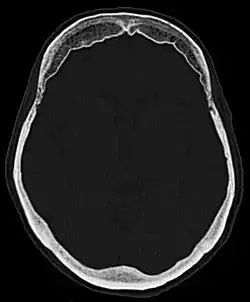

Hyperostosis frontalis interna

| Hyperostosis frontalis interna in a 74-year-old woman | |

Hyperostosis frontalis interna is a common, benign thickening of the inner side of the frontal bone of the skull. It is found predominantly in women after menopause and is usually asymptomatic. Mostly frequently it is found as an incidental finding discovered during an X-ray or CT scan of the skull.